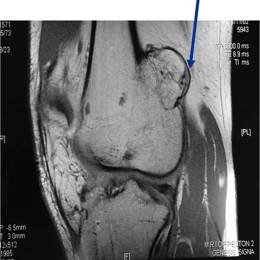

Radiographic imaging is used to help form a diagnosis. These include X-Ray, MRI, CT and Bone Scans

An example of an Osteochondroma MRI is shown.